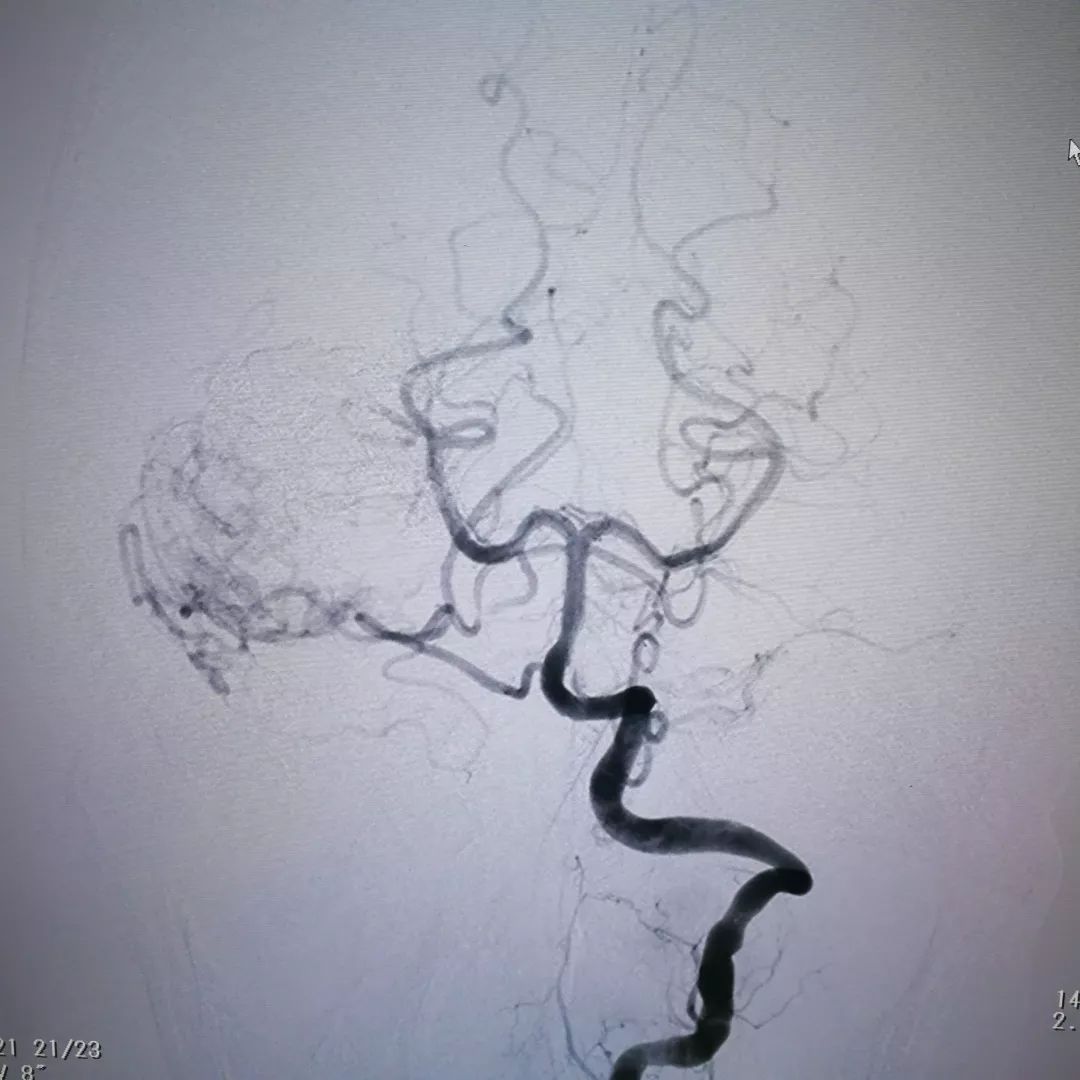

脑血管造影证实肿瘤血供极其丰富,血窦样结构充满血液,供血动脉粗大

通过介入栓塞,向肿瘤内注入栓塞物质(下图),填充并堵塞血窦,阻止流入到肿瘤内,从而降低手术

复查造影提示肿瘤内大部分血窦被堵塞,肿瘤内血液供应明显减少,从而达到降低手术风险减少术后并发症的目的